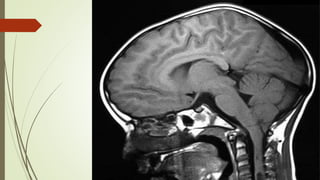

El estado de vigilia se mantiene por un sistema neuronal situado en la parte superior

del tronco encéfalo y el tálamo, el sistema reticular ascendente activador, y sus

conexiones con los hemisferios cerebrales.